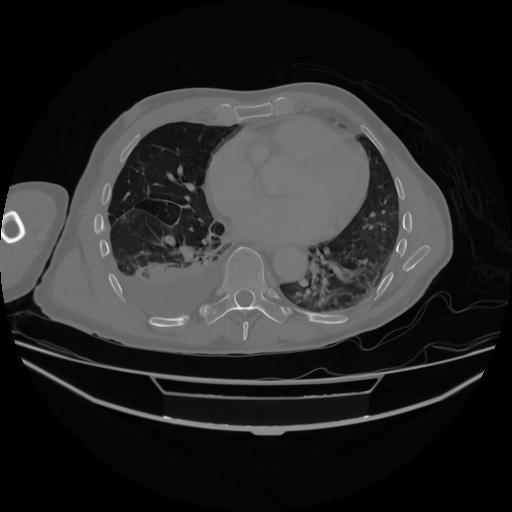

5 CUERPO,CE,Vol,1.0,CUERPO,,